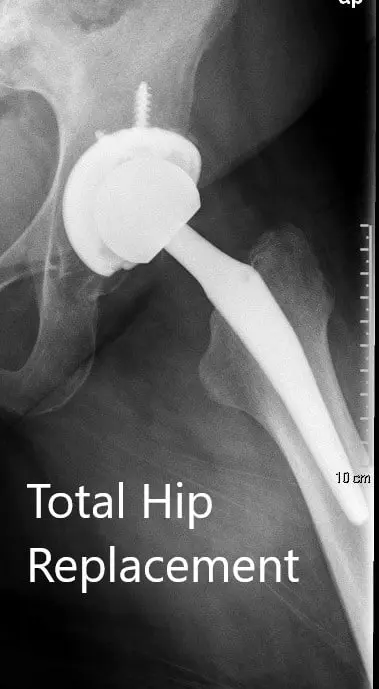

OPERATION: Left total hip arthroplasty using ceramic femoral head 36-mm plus 5 with 127-degree neck stem system size 5 with a 54-mm acetabular shell cluster hole with polyethylene insert with two screws.

Postoperative X-ray showing the AP view of the pelvis and lateral view of the left hip.